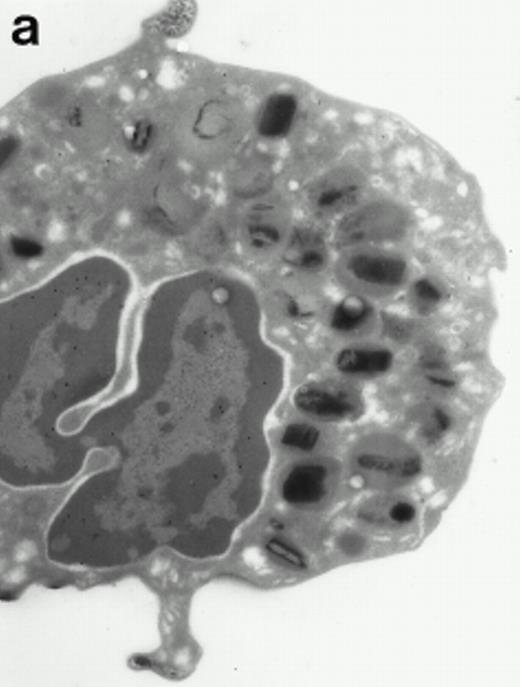

Morphologic analyses of both mature eosinophils and day-24 IL-5–induced UCC by immunoelectron microscopy were performed with proMBP-specific monoclonal antibody (J163-15E10) and with polyclonal antibody to MBP (rabbit #14). No proMBP staining was observed in peripheral blood eosinophils (Fig 6a); in contrast, MBP was localized specifically to the granule crystalline core (Fig 6b). Day-24 IL-5–induced UCC showed marked proMBP labeling of large uncondensed granules and minimal labeling of small condensed granules (Fig 6c); remarkably, proMBP was often seen as a ring around what appeared to be a granule in the process of condensing (black arrow). MBP labeling was confined primarily to condensing granules (Fig6d). Figure 7 shows results from double immunogold labeling of both proMBP (small gold) and MBP (large gold). ProMBP was concentrated in large uncondensed granules, and MBP was concentrated in condensed granules. Some granules (black arrow in Fig7b) contained labeling for MBP (primarily in the center) and proMBP (at the periphery). Controls using either normal mouse immunoglobulin or normal rabbit immunoglobulin as the primary label were negative (results not shown).

Localization of proMBP and MBP by immunoelectron microscopy. (a) A peripheral blood eosinophil labeled with anti-proMBP J163-15E10. Note the absence of specific labeling. (b) A peripheral blood eosinophil labeled with rabbit anti-MBP. Note that MBP is specifically localized to the granule crystalline core (black arrows). (c) Day-24 IL-5–induced UCC labeled with anti-proMBP. The black arrow shows localization of proMBP predominantly to the periphery of a condensing granule; very little proMBP is present in the interior of that granule. The white arrow points to a condensed granule, which lacks proMBP label. Also, note the presence of a large uncondensed granule densely labeled with proMBP proximal to the nucleus (open white arrowhead). (d) Day-24 IL-5–induced UCC labeled with anti-MBP. MBP is localized primarily to the interior of condensing granules (black arrows). (a, c, and d) Original magnification ×11,000; (b) ×15,000.